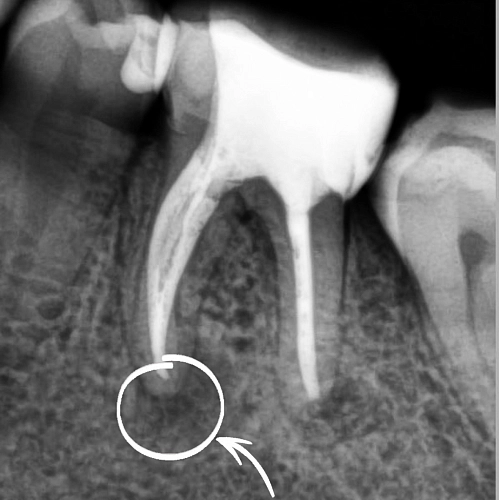

Пациент, обратился с жалобами на кровоточивость десен, неприятный запах изо рта. При осмотре был выявлен зуб, с негерметичной пломбой, провоцирующей застревание пищи и последующую кровоточивость десны. На рентгенологическом исследовании выявлен участок деструкции костной ткани. При снятии пломбы был неприятный запах из корневых каналов, что вызывало неприятный запах изо рта.

Через 6 месяцев после начала лечения наблюдалось значительное улучшение: уменьшение очага поражения и восстановление состояния десны. Рентгенологические исследования показали признаки регенерации костной ткани.